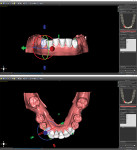

The optically scanned model of the lower arch was opened in the 3D modeling application to evaluate the integrity of the model, trim off any unnecessary data from the border using the cut tools, and repair any flaws using the analysis repair tool. After the model was corrected and smoothed, the teeth were assessed for degree of rotation, alignment, torqueing, and inclination or retraction. To ensure the correct rotation of the teeth, it is best to create "buttons" on the facial aspects of the canines. This facilitates positive seating and helps predict the planned intrusion of the incisors without resulting in unseating of the aligner. The STL file for the newly refined model was then exported to the planning software for aligner design (Figure 10).

Using the STL file, a new project was started in the planning software's orthodontic module. The positions of the teeth were designated to help the software identify each individual tooth and generate approximate margin tracings. Next, the margins of the teeth were refined, and the software segmented each tooth for individual movement (Figure 11). The teeth were then aligned to their final desired positions, and the rate of movement (ie, weekly, bi-weekly, monthly) was selected (Figure 12 and Figure 13). Using known averages of acceptable tooth movement and sequencing, the software then ran its algorithm and determined the sequential steps of alignment for review. Once approved, the software created individual models for each progressive stage of treatment (Figure 14). After identification labels were digitally embossed onto the models and an orthodontic report for the progressive movement of each tooth was exported and attached to the patient's chart, the STL files for each of the models were ready to be exported for 3D printing.